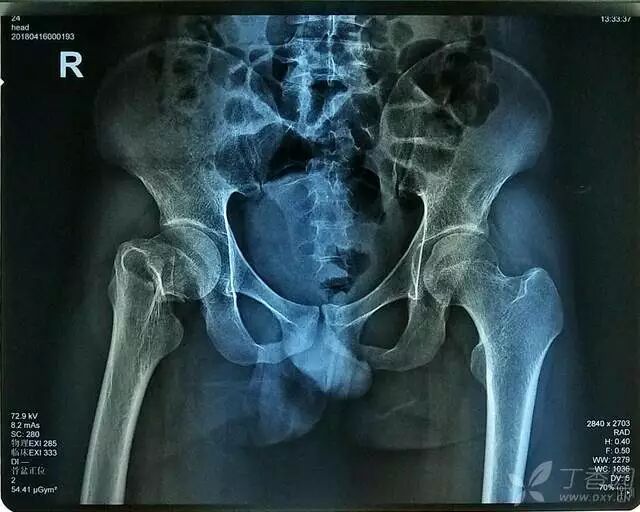

患者,男,23 岁,因「摔伤致右髋部肿痛、活动受限 6 小时」入院。

查体:右下肢无明显短缩,明显外旋畸形,右髋部轻度肿胀,未见明显皮下瘀斑、无皮肤擦伤等。右侧腹股沟中点固定压痛,右侧股骨大粗隆叩击痛及右下肢纵向叩击痛(+),右髋关节主被动活动均明显受限;右足踝等关节活动正常,右下肢末梢血运正常,各足趾的感觉、活动等均正常。

辅助检查:CT 检查提示右侧股骨颈骨皮质不连续,可见透亮骨折线及碎骨片影,断端错位、成角,周围软组织肿胀;右侧髋臼后下缘及左侧耻骨上支骨皮质不连续,断端未见明显错位;右侧髋臼后缘见类圆形稍低密度影,大小约 5*9 mm,边界清楚,边缘见硬化边;右侧髋关节在位,关节间隙未见明显变窄。

初步诊断:右股骨颈骨折(经颈型)